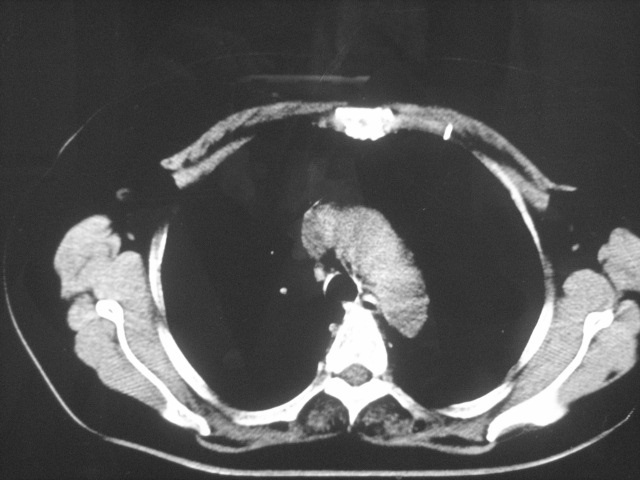

以下是引用清清楚楚在2007-8-28 7:13:00的发言:[br]右肺下叶可见斑片状高密度影,边缘模糊;右肺中叶内侧段及左肺舌段亦可见小斑片状模糊影。[br]考虑双肺感染,建议抗炎治疗后复查。

以下是引用天南地北在2007-8-27 23:49:00的发言:[br]右肺下叶可见斑片状高密度影,边缘模糊;右肺中叶内侧段及左肺舌段亦可见小斑片状模糊影。[br]考虑双肺感染,建议积极抗炎治疗后复查。

以下是引用天南地北在2007-8-27 23:49:00的发言:[br]右肺下叶可见斑片状高密度影,边缘模糊;右肺中叶内侧段及左肺舌段亦可见小斑片状模糊影。[br]考虑双肺感染,建议抗炎治疗后复查。

以下是引用难听在2007-8-28 13:17:00的发言:[br]右肺下叶背段支气管狭窄,是否可以考虑新生物伴阻塞性肺炎.请大家帮帮忙,这个病人是卫生局长的丈母娘.惹不起啊.